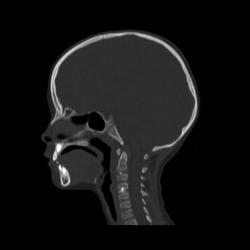

Ребенок 6 лет. Жалобы на выраженные боли в шейном отделе позвоночника. Со слов матери, боли в шее беспокоили длительное время. 2 недели отмечалась незначительная травма - девочка резко повернула голову в сторону, боли в шее услились. В настоящий момент  отмечаются выраженные боли в шее, резкое ограничение движений, повышение температуры тела, воспалительные изменения в анализах, (возможно, связанные с пиелонефритом, который также имеет место). Поступала с направительным диагнозом "ротационный подвывих атланта", однако данные рентгенографии заставили расширить круг диагностического поиска.Родовую травму мать отрицает. Хотелось бы узнать мнение уважаемых коллег.

Уважаемая коллега! С точки зрения классической рентгенологии (с учётом качества представленных снимков) могу высказать следующее:

- определяется выраженный антелистез тела С5;

- двуконтурность тел С3 и С5 может свидетельствовать о нарушении целостности костной ткани указанных тел позвонков;

- безусловно, межпозвонковые диски "поехали".

Вижу ещё раздвоенный axis.

Аксис не раздвоен, это нормальная картина для шести лет, просто верхушка зуба еще хрящевая.

Спасибо. Буду знать. По заданной теме: не хотелось бы быть освистанным, но смею предположить ювенильный ревматоидный артрит.

Случай помню. Закончилось все на удивление просто - после недели вытяжения петлей Глиссона боли ушли, движения в ШОП восстановились в полном объёме. Рентгенологические данные расценили как врожденную аномалию развития. Воспалительные изменения в анализах - как проявления пиелонефрита. В любом случае, из нашего поля зрения ребёнок ушел к нефрологам.